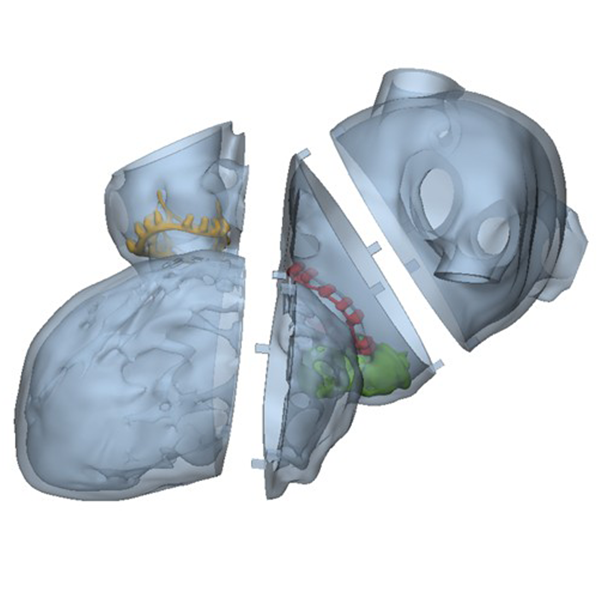

Figure B (Right): Interactive 3D model of the proposed print. The left atria is presented in transparent grey, the left ventricle is opaque grey, the mitral valve is yellow, the mitral plug is green, and the aortic valve is red.

Figure C: A side view of the proposed 3D print, showing the modular design with square pegs used to align and hold the sections together.